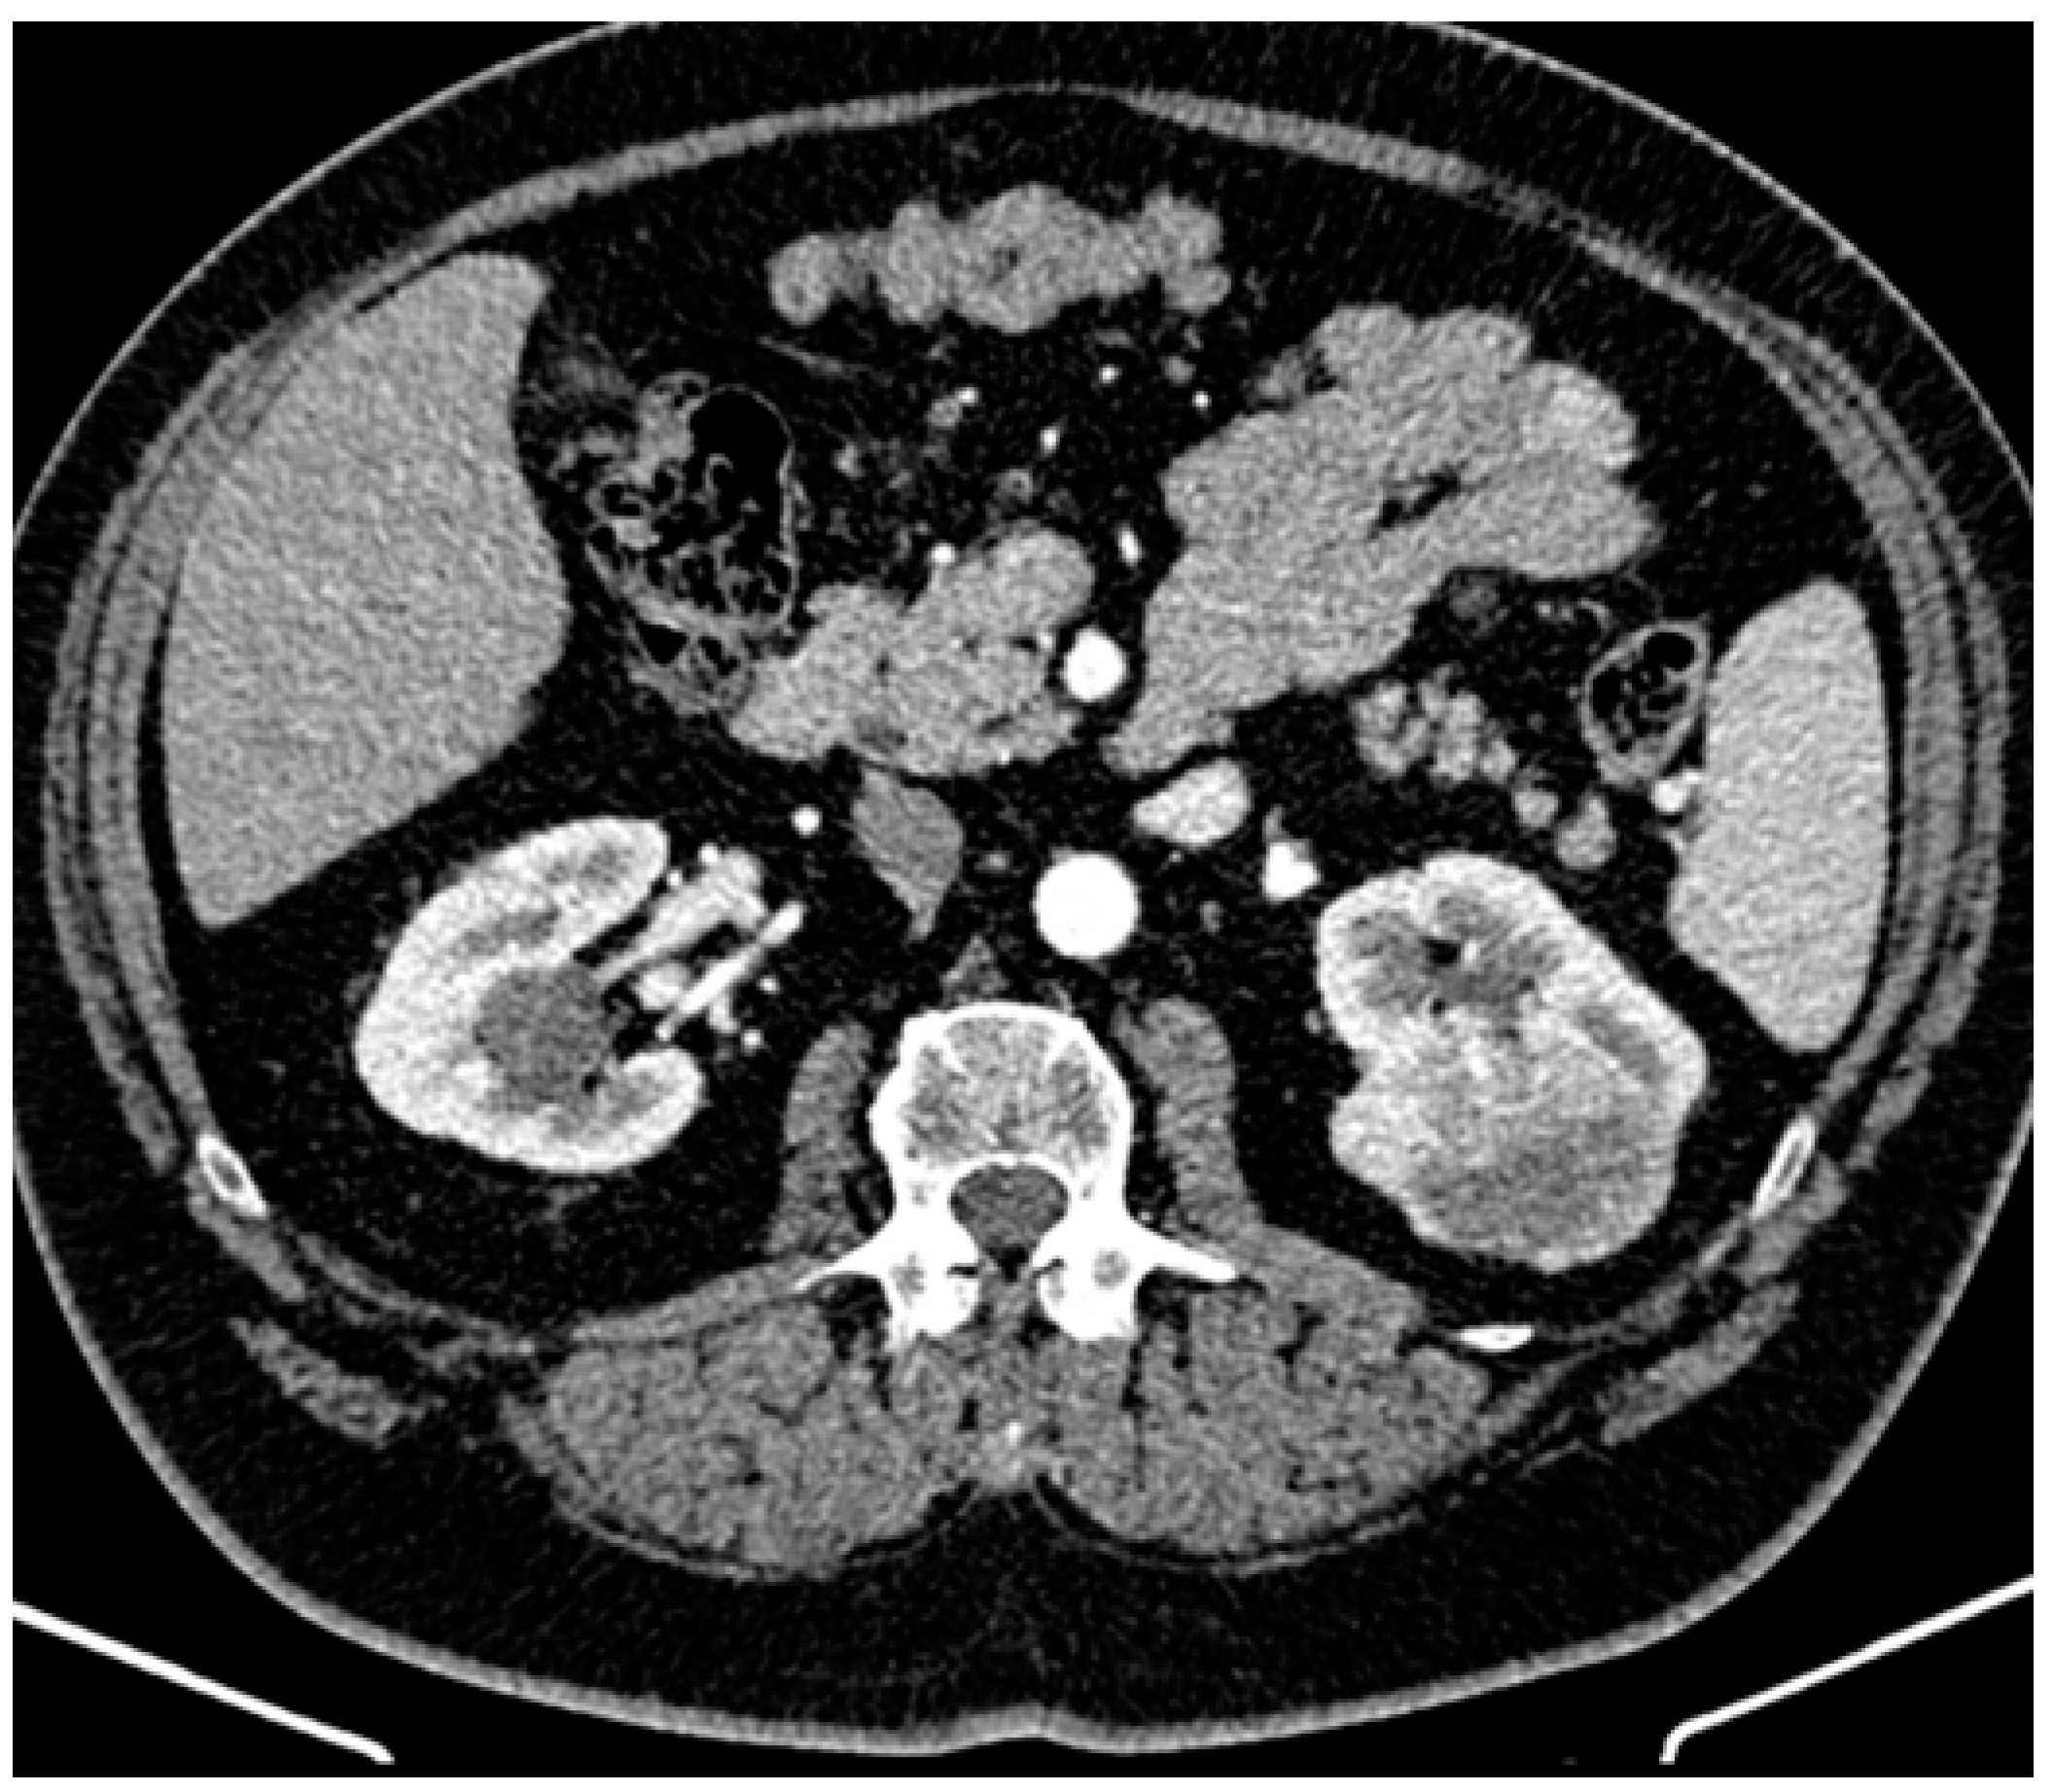

2. Case Presentation